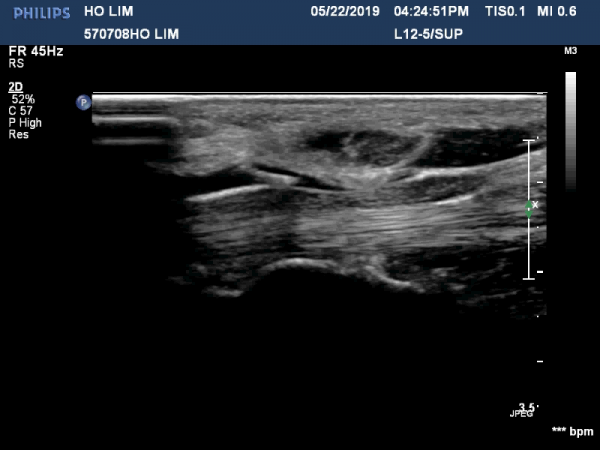

¼ö±Ù°ü ±ÙÀ§ºÎ(scaphoid, lunate level)¿¡¼ Á¤Á߽Űæ Ⱦ´Ü¸é°Ë»ç»ó Á¤Á߽ŰæÀÇ Àú¿¡ÄÚ ºÎÁ¾ÀÌ °üÂûµÊ.(»çÁø 2).